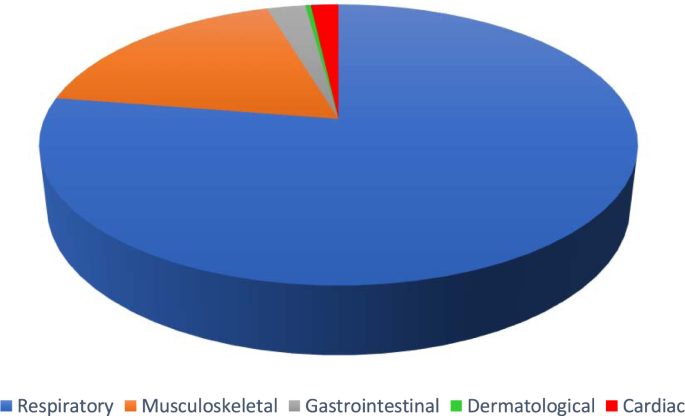

A team of resident doctors in internal medicine, physiatry, anatomical pathology and family medicine, and senior Canadian medical students created this dataset. The medical interviews were recorded in the format of Objective Structured Clinical Examinations (OSCE) 1 . 272 cases were simulated between the physician and the patient. These cases were recorded and classified into the categories of respiratory, musculoskeletal, cardiac, dermatological, and gastrointestinal diseases. However, the majority of simulations were respiratory cases. Please see Fig. 1 for a visual representation of the types of cases included. These audio recordings were then transcribed, manually corrected for speech to text errors, and an identifier was added to specify the speaker.

Pie chart demonstrating the proportion of cases in the following categories: respiratory (78.7%, blue), musculoskeletal (16.9%, orange), gastrointestinal (2.2%, grey), cardiac (1.8%, red) and dermatological (0.4%, green).

272 cases were simulated and recorded (please refer to Fig. 1 ). The focus of the dataset was respiratory cases (214 cases). In addition, 46 musculoskeletal cases, 5 cardiac cases, 6 gastrointestinal cases and 1 dermatology case were also simulated. Of the total simulated recordings, 57% of the cases involved a male physician and 43% involved a female physician. From the patient perspective, 55% of the simulated cases involved a male patient and 45% involved a female patient. The average duration of each conversation was 11 minutes and 56 seconds. For further details, please refer to Fig. 2 for a histogram of the number of cases corresponding to various lengths of time. The focus was on respiratory cases because most pandemics, including the COVID19 pandemic, are caused by droplet or airborne based respiratory diseases. Therefore, it is crucial to differentiate between a benign cause of malaise such as the common cold from a highly infectious and fatal cause such as COVID19 or Tuberculosis.